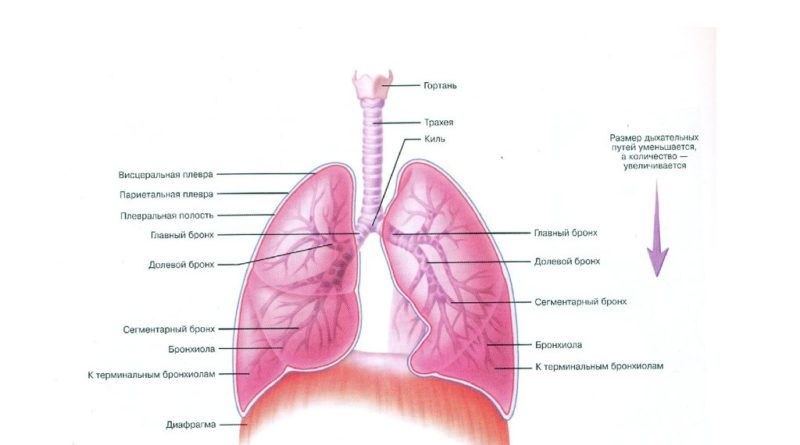

В трахеобронхиальном дереве в организме человека вырабатывается небольшое количество слизи, предусмотренное природой для удаления из органов дыхания микробов и чужеродных примесей (пыли, мелких частиц и соединений, неизменно присутствующих в воздухе).